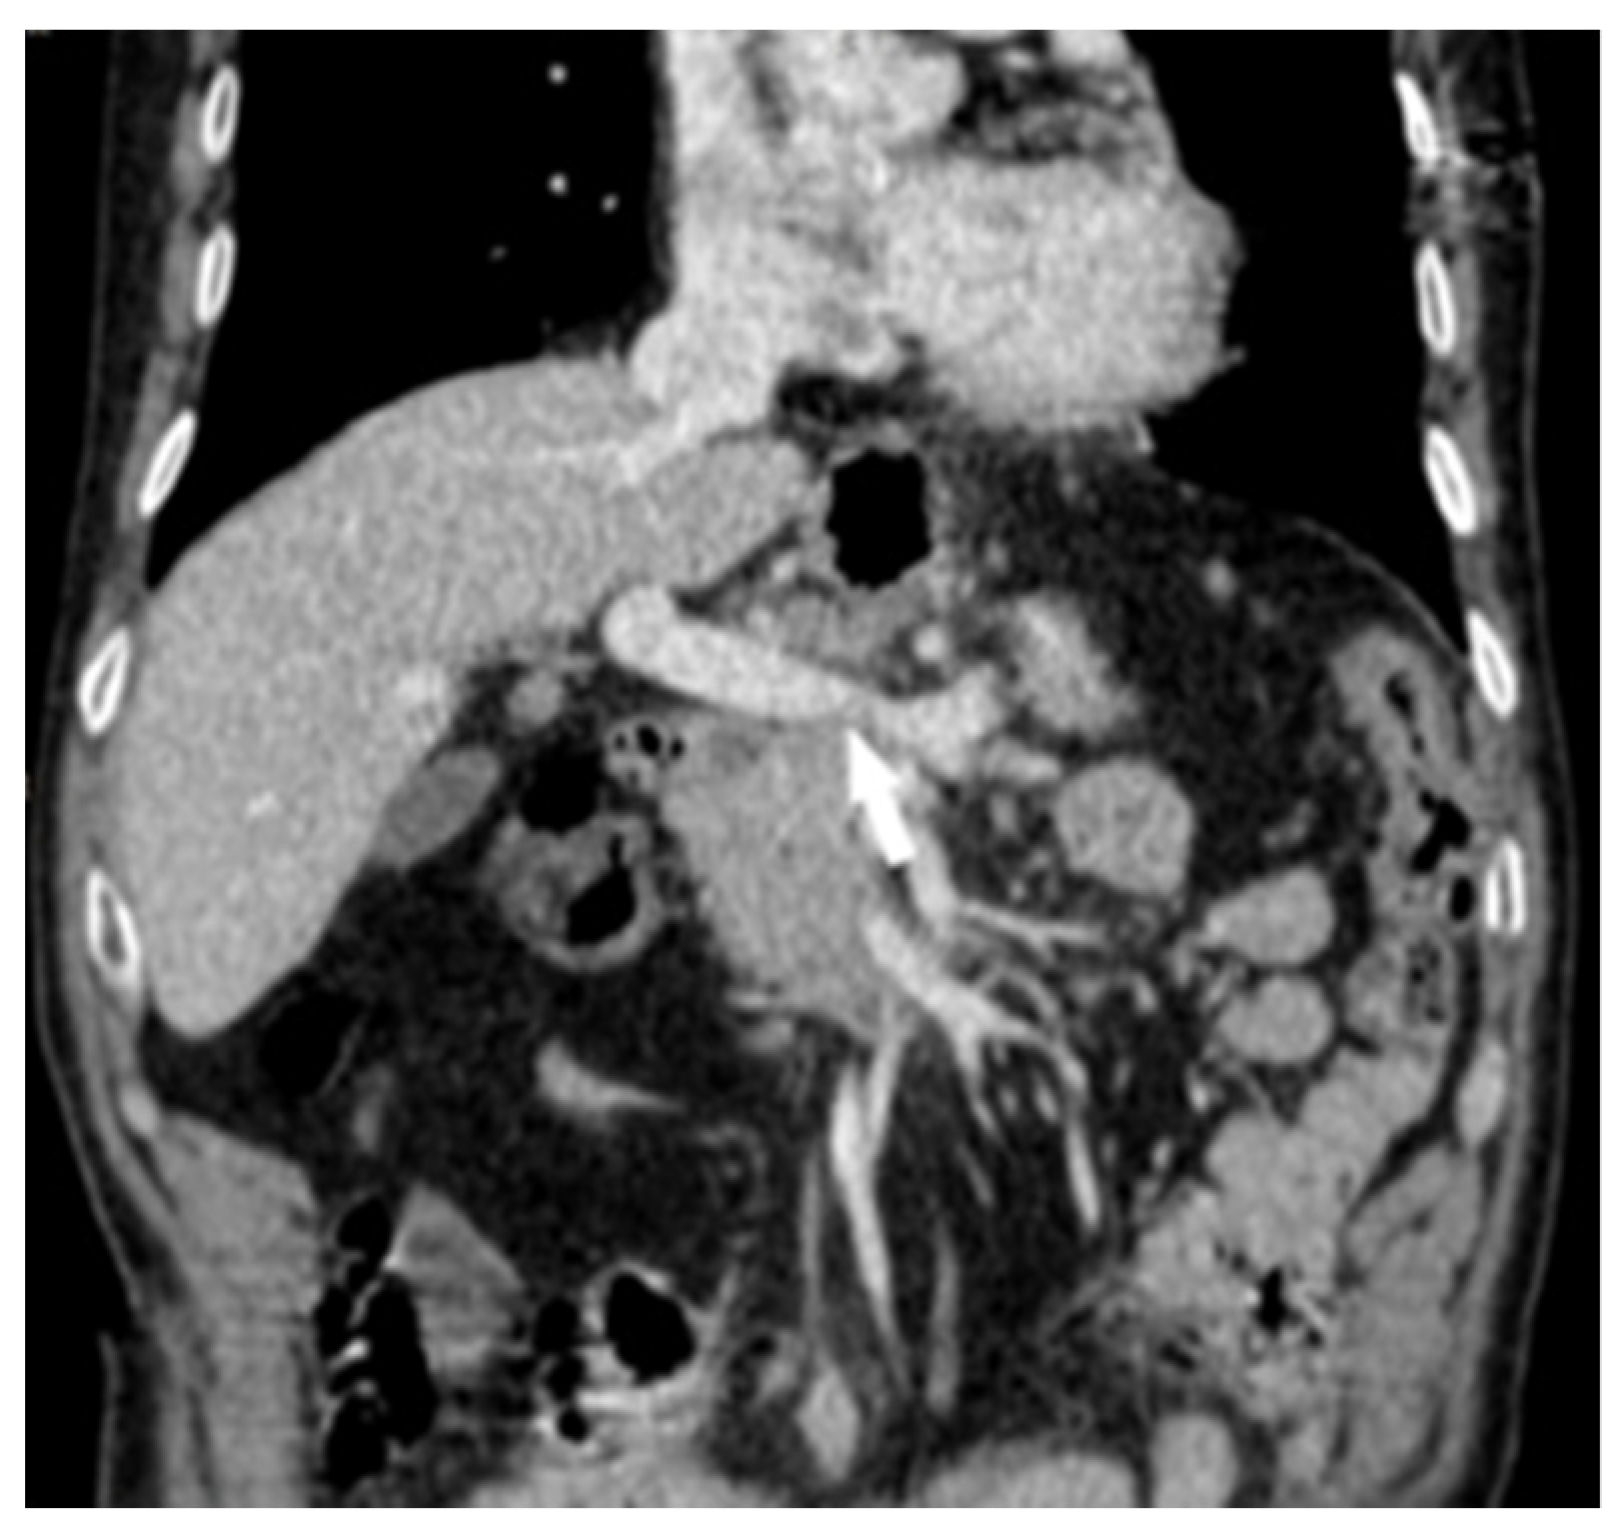

2. Case Report